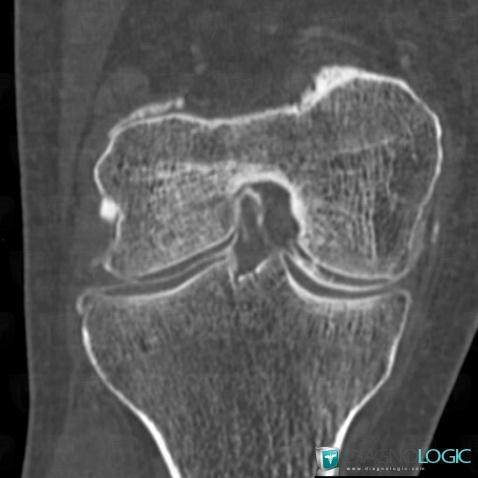

Degenerative joint disease, Femorotibial joints - Intercondylar notch, CT

Here is the specific information in the key image above:

- Diagnosis Degenerative joint disease, Location(s) Femorotibial joints - Intercondylar notch, with gamuts